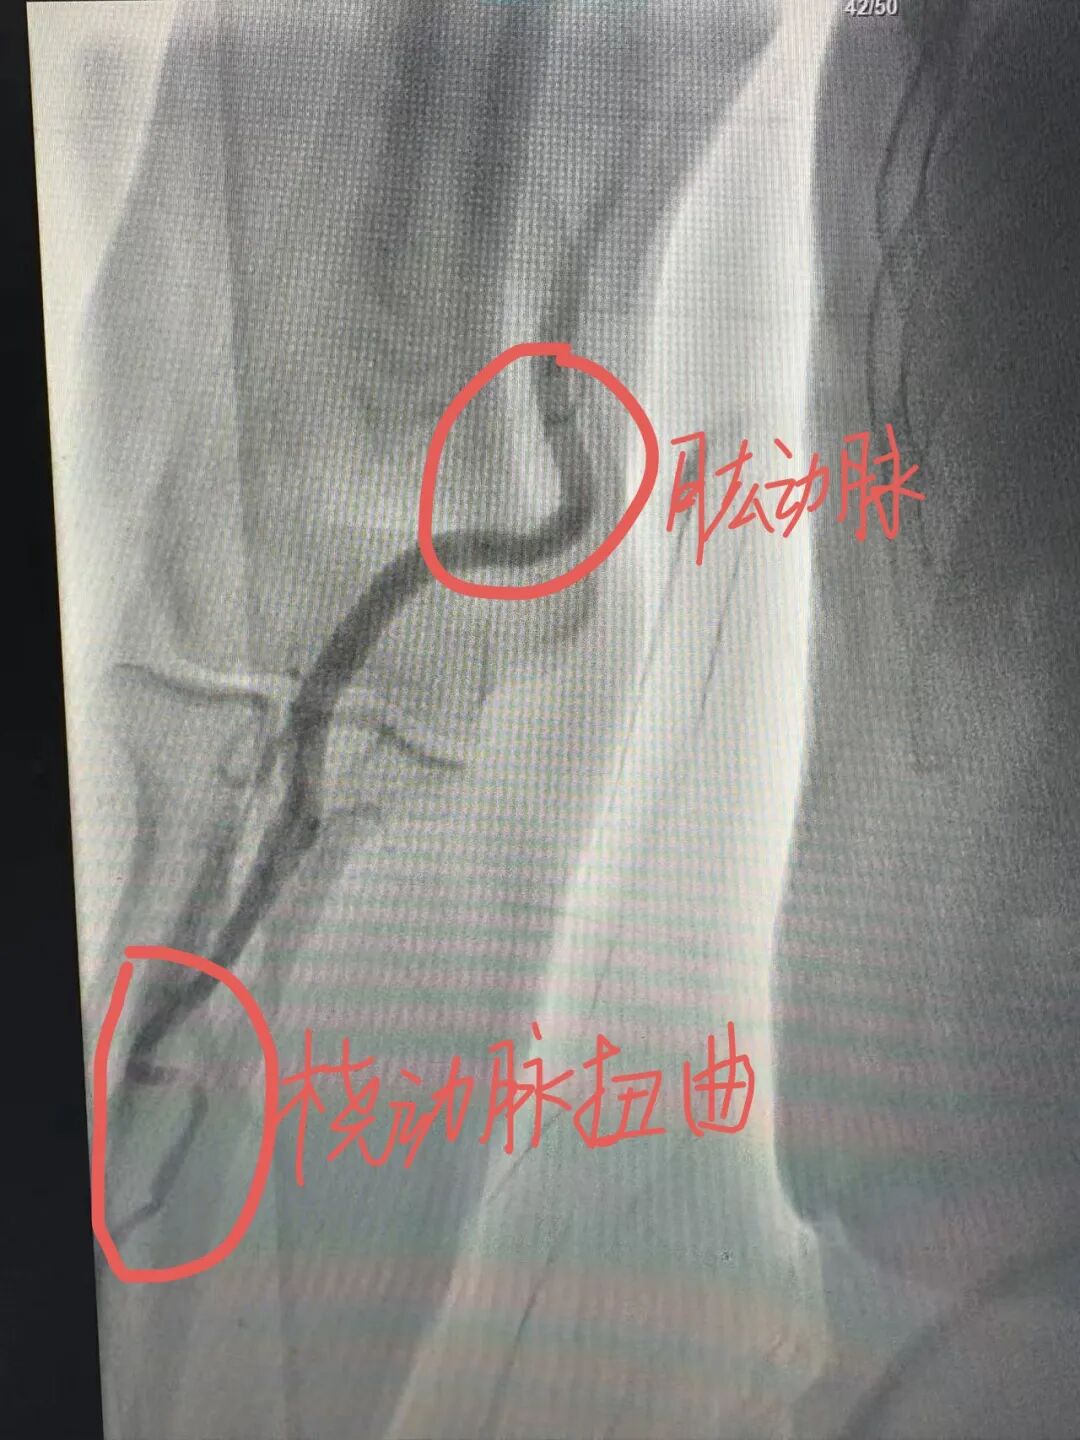

介入术中发现,在常规右侧桡动脉入路时,发现患者的桡动脉、肱动脉、锁骨下动脉血管严重扭曲,仿佛是一条蜿蜒曲折、布满荆棘的山路,导丝难以通过,手术一度受阻。关键时刻,介入团队冷静应对,主治医师罗科伟凭借娴熟技术与对血管结构的精确把握,耐心调整导丝方向,最终顺利将其送至主动脉根部,成功完成造影。